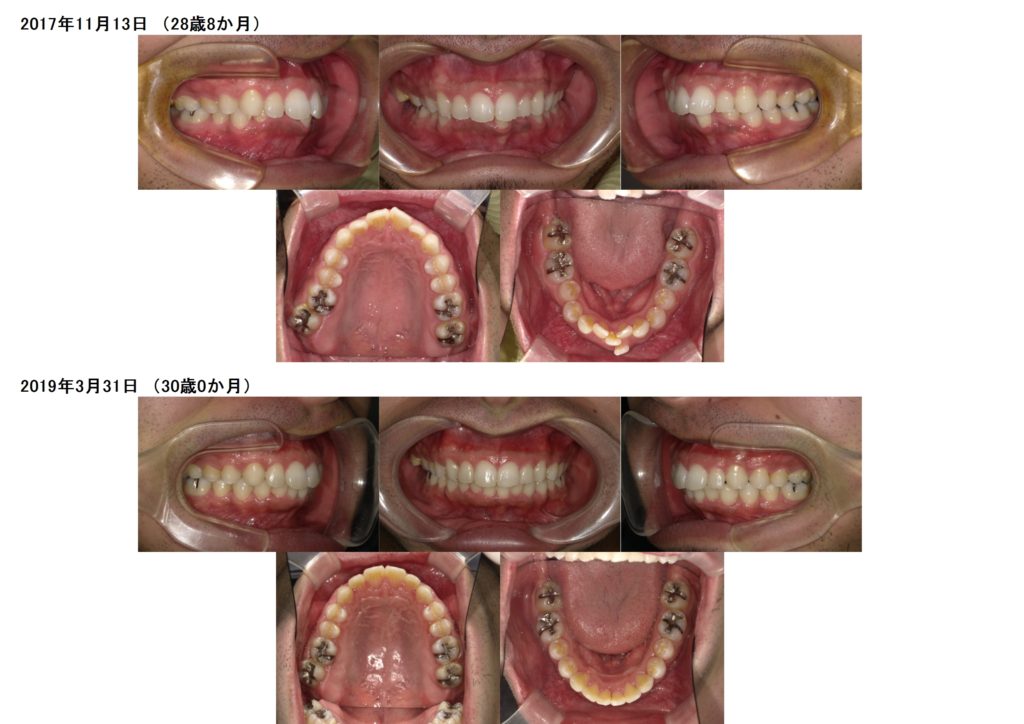

男性の方でもこのようにブラケット治療をされますよ☆

思っていたより、気づかれなかった。そんなに目立たないですね。と言われる方も多いですよ。

とってもキレイになりましたよね!!